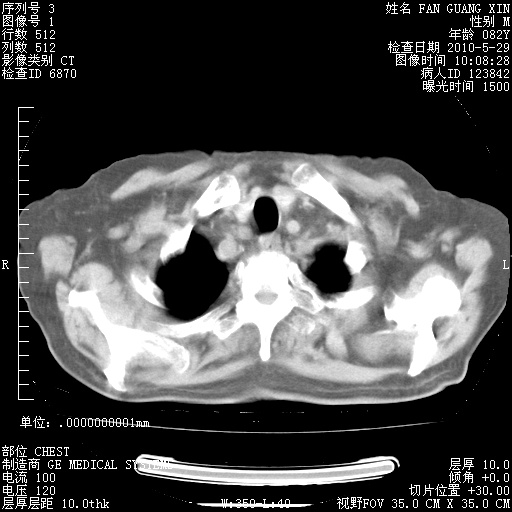

再治疗10天后的肺部CT

阅读此次胸部CT,肺间质渗出性改变较入院时有吸收。目前从体温、白细胞、中性分叶明显增高,肯定存在细菌感染(发生医院感染哦,若无消化道及泌尿系统等感染的依据,肺部感染可能大)。若你院头孢哌酮舒巴坦钠耐药率较高,同意你的方案,若48小时体温仍高,可考虑使用碳青霉稀类抗菌药物,同时可予超声雾化、注意滴数时加大液体量。白蛋白33.30g/L较低哦,需加强营养等支持治疗。